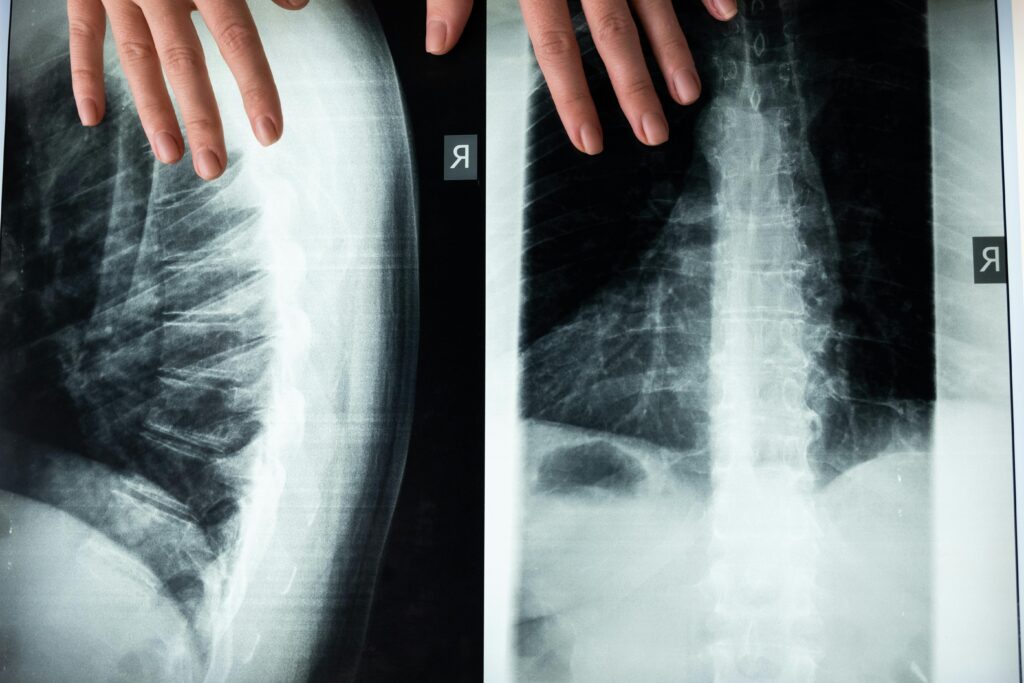

Intervertebral discs are made of a gel-like core (nucleus pulposus) surrounded by a fibrous outer layer. Surrounding that is a different cartilage that serves to contain the inner nucleus. This outer ring is called the annulus. Over time, aging, repetitive strain, or injury can cause these discs to dry out, weaken, and collapse. This process, known as disc degeneration, affects nearly 60% of people over the age of 60. It is correlated to the osteoarthritis process in other joints.

When discs degenerate, they lose their ability to cushion the spine, leading to pain, stiffness, inflammation, and in severe cases, nerve compression. While common treatments only target pain and inflammation, they cannot rebuild the cartilage or repair the disc structure. That’s why the question, “Can stem cells regenerate spinal discs?” has become so important.